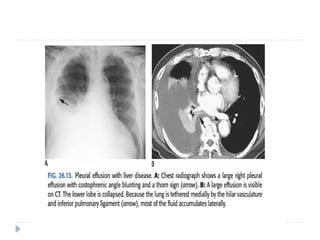

 Chest radiographs show a biconvex, spherical, or elliptical

 An effusion in the right minor fissure should be

distinguished from right middle lobe atelectasis

 The following features help in differentiation:

− The effusion is biconvex while lobar atelectasis is flat or

concave.

− Only atelectasis obliterates the right cardiac border

− Atelectasis obscures the interlobar fissure but an effusion

preserves the contour of the fissure as a linear structure in

its peripheral portion

 When the Subpulmonic effusion is left-sided, the distance between the

inferior surface of the left lung and the gastric bubble measures more

than 2 cm.